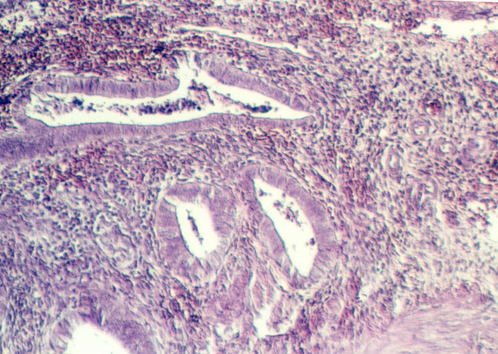

The uterus communicates with the outside world via a short canal called the cervix. The following photograph shows the uterus in the proliferative stage. The glands continue into the cervix in the left side of the photo.

The cervix continues and joins with the vagina. The cervix is lined by simple high columnar epithelium which consists of mucous cells. These are shown in the following views. In the lowest magnification, one can see bundles of smooth muscle in the wall (see below)